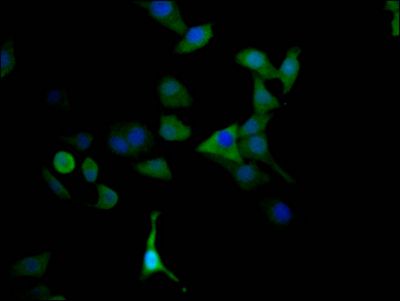

Immunofluorescence staining of HepG2 Cells with CSB-RA250615A0HU at 1:50, counter-stained with DAPI. The cells were fixed in 4% formaldehyde, permeated by 0.2% TritonX-100, and blocked in 10% normal Goat Serum. The cells were then incubated with the antibody overnight at 4℃. Nuclear DNA was labeled in blue with DAPI. The secondary antibody was FITC-conjugated AffiniPure Goat Anti-Rabbit IgG (H+L).